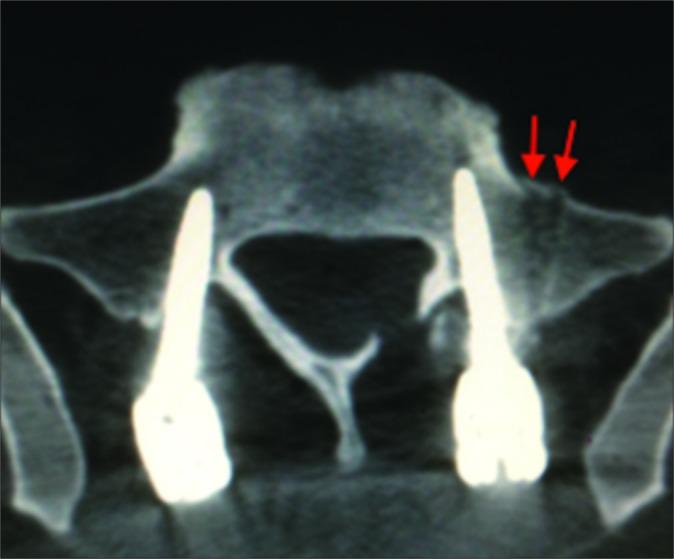

tEMG, somatosensory-evoked potential (SSEP), and transcranial electrical motor-evoked potential (TcMEP) data were retrospectively reviewed from 2015 to 2017 during open posterior lumbosacral instrumented fusions. We utilized screw stimulation alert thresholds of <14 mA (tEMG) and recorded from the lower extremity muscles and anal sphincter. Furthermore, all patients underwent routine postoperative computed tomography (CT) scans to confirm the screw location.

There were 106 S1 screws placed in 54 patients: 52 bilateral and 2 unilateral. In 6 patients (11.1%), 7 screws (6.6%) registered at low tEMG thresholds. In 1 patient, the postoperative CT scan documented external malposition of the screw despite no intraoperative IOM/tEMG alert. When S1 misplaced screws were stimulated, the most sensitive muscle was the tibialis anterior; the sensitivity of the IOM/tEMG was 87.5%, the specificity was 97.9%, the positive predictive value was 77.8%, and the negative predictive value was 98.9%. TcMEP and SSEP did not change during any of the operations. Notably, no patient developed a new neurological deficit.

Anterolateral S1 screw malposition can be detected accurately utilizing IOM/tEMG stimulation of screws. When alerts occur, they can largely be corrected by partially backing out the screw (e.g., a few turns) and/ or changing the screw trajectory.